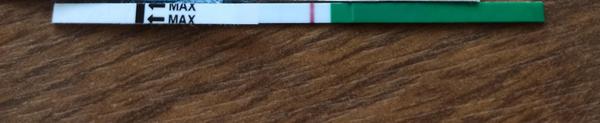

@noemikatka vďaka 🤗noo to je mamatest a keďže nikde som ho nezohnala tak som objednala z internetu,chces stránku?objednalavala som v pondelok poobede a v stredu ráno tu už boli 😊

Baby zaujíma ma či na tomto niečo vidíte,alebo nie,toto je v limite